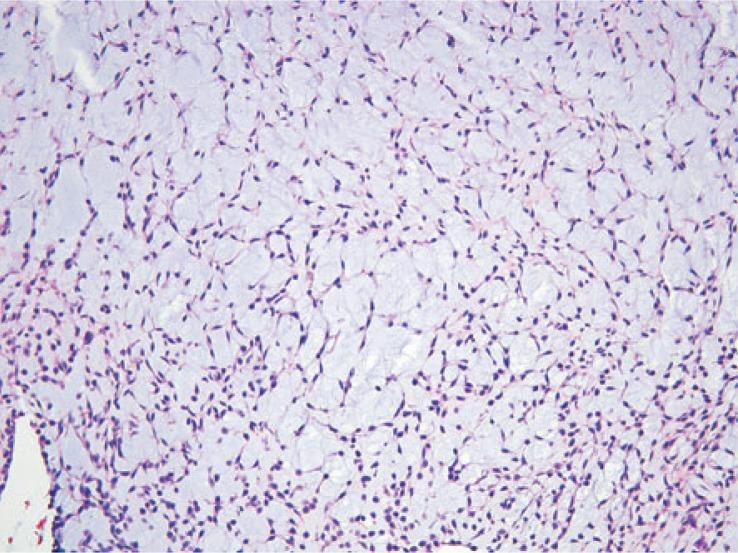

The aim of the study was to evaluate the clinical and imaging features of extraskeletal myxoid chondrosarcoma (EMC) including initial presentation, recurrence, and metastases.

Among 13 patients, 3 died during the timeframe of this study. Nine patients had primary tumor in the lower extremity, and average tumor size was 9.3 cm (range 3.3-18 cm). On MRI, primary tumors were hyperintense on T2, isointense to muscle on T1, and demonstrated peripheral/septal enhancement. Three patients had local recurrence and 12 had metastatic disease, with lung involvement being the most common. Tumor density on contrast enhanced CT ranged from 8.2 to 82.9 Hounsfield unit (HU). FDG-PET/CT imaging was performed in 3 patients. One patient had no FDG avid disease and 2 patients had metastatic disease with standard uptake values (SUV) of 2.8 and 7.4. The patient with intense FDG uptake demonstrated more solid appearing tumor burden and had the shortest survival.

EMC is a rare tumor that often occurs in the lower extremities and frequently metastasizes to the lungs. Increased tumor density and increased FDG uptake may be related to more aggressive disease.